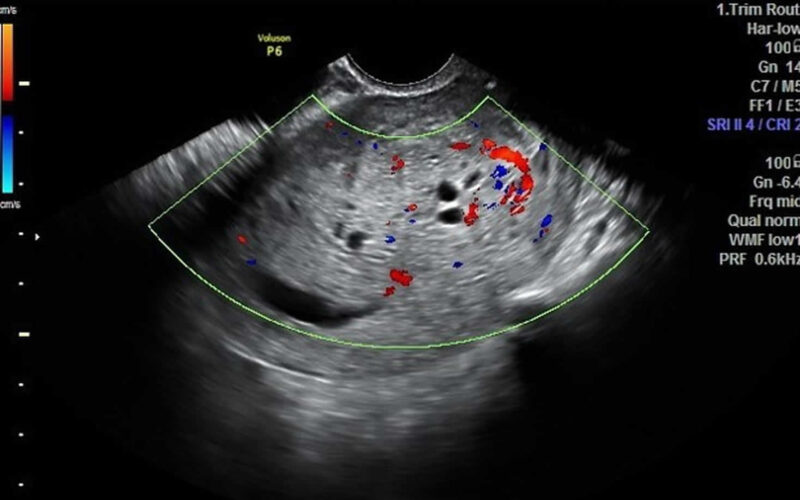

La mola hidatiforme o embarazo molar se da si un embrión inviable sigue desarrollándose en el útero.

Existen dos tipos de mola hidatiforme: la completa y la parcial. Hablamos de embarazo molar completo cuando el tejido fetal no llega a desarrollarse en ningún grado y la placenta se encuentra inflamada, tiene un aspecto poco habitual y forma quistes llenos de líquido. En los casos de mola completa en ocasiones ni siquiera se forma la placenta.

En ocasiones pueden observarse un agrandamiento del útero o un crecimiento demasiado rápido del útero en relación al progreso del embarazo, así como quistes en los ovarios o en la vagina. Cabe destacar también la preeclampsia, que se asocia con un incremento de la presión de la sangre y con la presencia de determinadas proteínas en la orina.